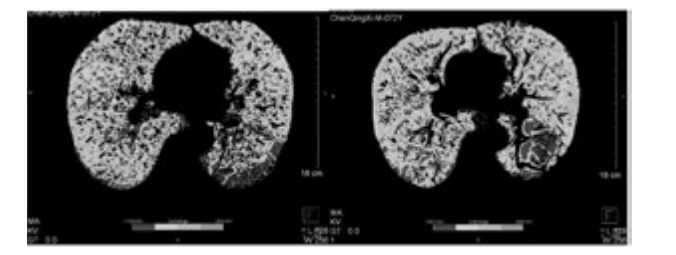

例1患者行干細胞移植前后肺部 CT 檢查

下圖為雙源CT肺實(shí)質(zhì)分析軟件,深藍色表示CT值在-1000 至-951,治療后較治療前深藍色面積明顯縮小。

雙源CT肺實(shí)質(zhì)分析軟件

從表3、表4提示,CT 值在-1000 至-951 比例有所下降,Class4( % ) 亦明顯下降,故肺氣腫較治療前好轉。